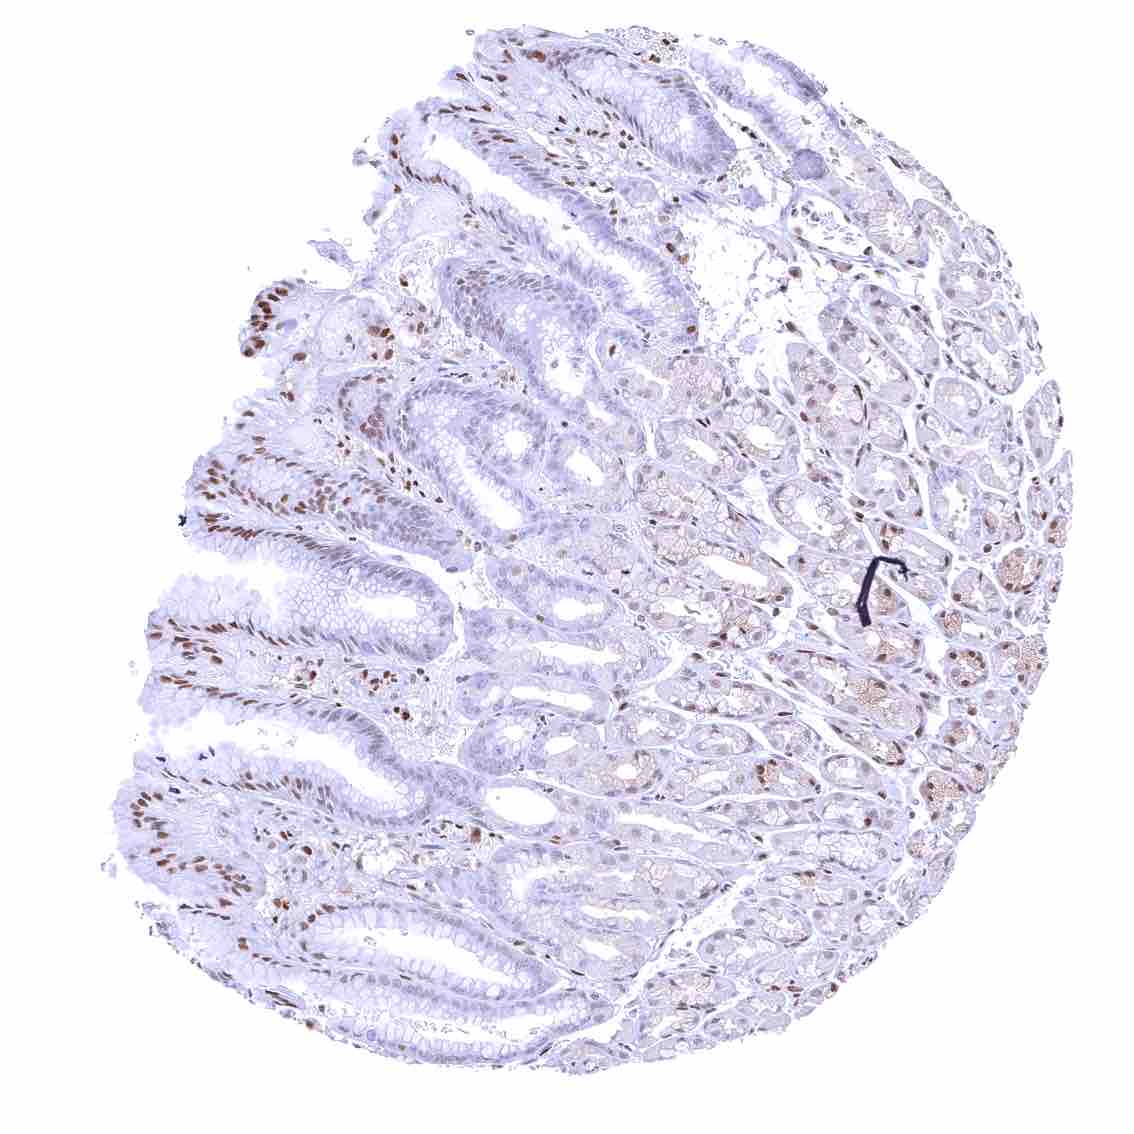

Rectum, mucosa